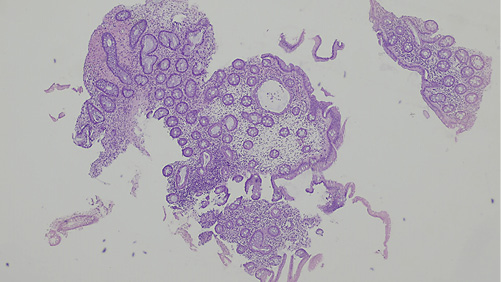

Fig. 2 Pathological findings with hematoxylin and eosin stain (×40): normal crypt architecture and a congestive edematous lamina propria with minimal inflammatory infiltrate suggesting reactive changes.

A 51-year-old man, former smoker (20 pack-years), with hemorrhoidal disease, irritable bowel syndrome, pulmonary emphysema and a mechanical prosthetic aortic valve under warfarin, presented for post-polypectomy surveillance colonoscopy. He complained of frequent tenesmus, diarrhea (2-3 liquid dejections in the morning), bloating and abdominal discomfort. Several polypoid grape-like submucosal masses were identified in a 10-cm segment of the descendent colon (Fig. 1a, b). Since the lesions were easily indented with gentle pressure and had a bluish hue, pneumatosis cystoids intestinalis (PCI) was suspected. Biopsy of one of these masses caused immediate deflation, confirming the diagnosis. Histopathological evaluation showed normal crypt architecture and a congestive edematous lamina propria with minimal inflammatory infiltrate suggesting reactive changes (Fig. 2). The patient had no history of abdominal trauma and no pharmacological (alpha-glucosidase inhibitors, steroids) or infectious (Clostridioides difficile, tuberculosis, human immunodeficiency infection) causes. Over a long-term follow-up of 12 years, the mild symptoms were managed conservatively with loperamide, spasmolytics and probiotics, which showed an improvement. In this period, two surveillance colonoscopies were performed showing the same unchanged endoscopic findings described above. Recently, due to surveillance of an ascending aortic aneurysm, a contrasted chest computed tomography (CT) identified a small pneumoperitoneum in the left subphrenic region. Abdominal CT extension showed more free peritoneal air in the left hypochondrium and air bubbles adjacent to the lumen of the bowel, some of them being subserosal (Fig. 3a, b).